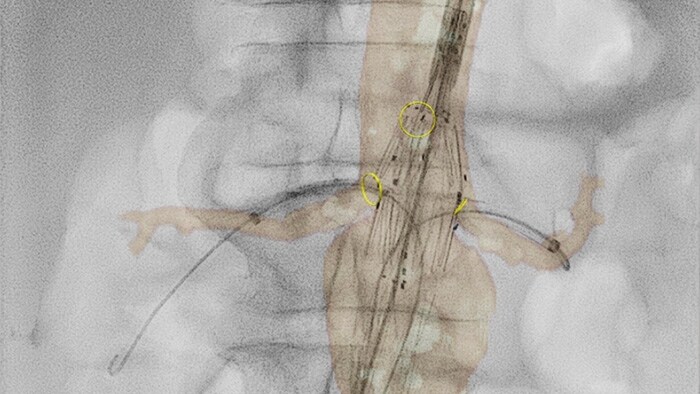

VesselNavigator proporciona una hoja de ruta 3D, intuitiva y continua, basada en conjuntos de datos de la angiografía por tomografía computarizada (ATC) y la angiografía por resonancia magnética (ARM) existentes para guiarlo a través de la vasculatura durante los procedimientos aórticos. En un estudio se demostró un promedio de 170 ml de reducción del contraste durante la reparación endovascular de aneurismas aórticos complejos con el uso de la guía de fusión de imágenes de la ATC de VesselNavigator.1 En otro estudio se mostró una reducción en el tiempo promedio del procedimiento de 6,3 a 5,2 (1,1) horas durante la FEVAR/BEVAR con la guía de fusión de imágenes de la ATC de VesselNavigator.2

La ecografía intravascular (EIV) es una tecnología de imágenes basada en catéteres que permite a los médicos visualizar los vasos sanguíneos de adentro hacia afuera para ayudar a evaluar la presencia y el alcance de la enfermedad. La EIV ayuda a decidir, guiar y confirmar el tratamiento intervencionista adecuado para cada paciente.